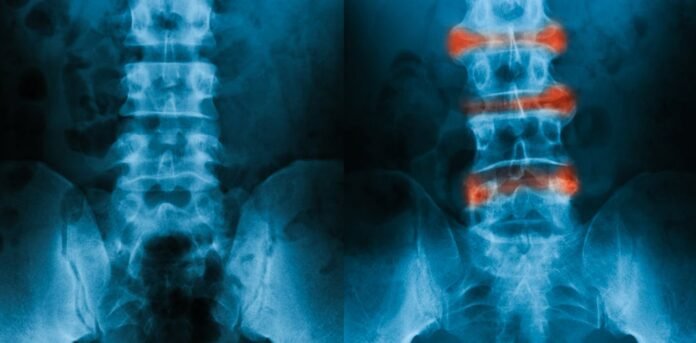

Ankylosing spondylitis (AS) is the second most common type of inflammatory arthritis, often affecting teenagers and young adults. Symptoms of AS can include back pain, stiffness, joint inflammation (arthritis), inflammation where tendons attach to bones (enthesitis), and fatigue. Over time, these symptoms can lead to spinal fusion, which significantly affects quality of life, particularly in young people.

Unfortunately, diagnosing AS can be a lengthy process, taking up to ten years from the onset of symptoms and usually requiring X-rays. The slow progression of the condition, coupled with the lack of a definitive test, contributes to these delays.